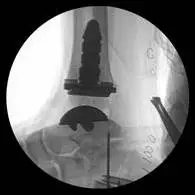

These are pics of the fusion prior to takedown

These first three pics are placement of screws in the medial malleolus and distal fibula to aid in stability.